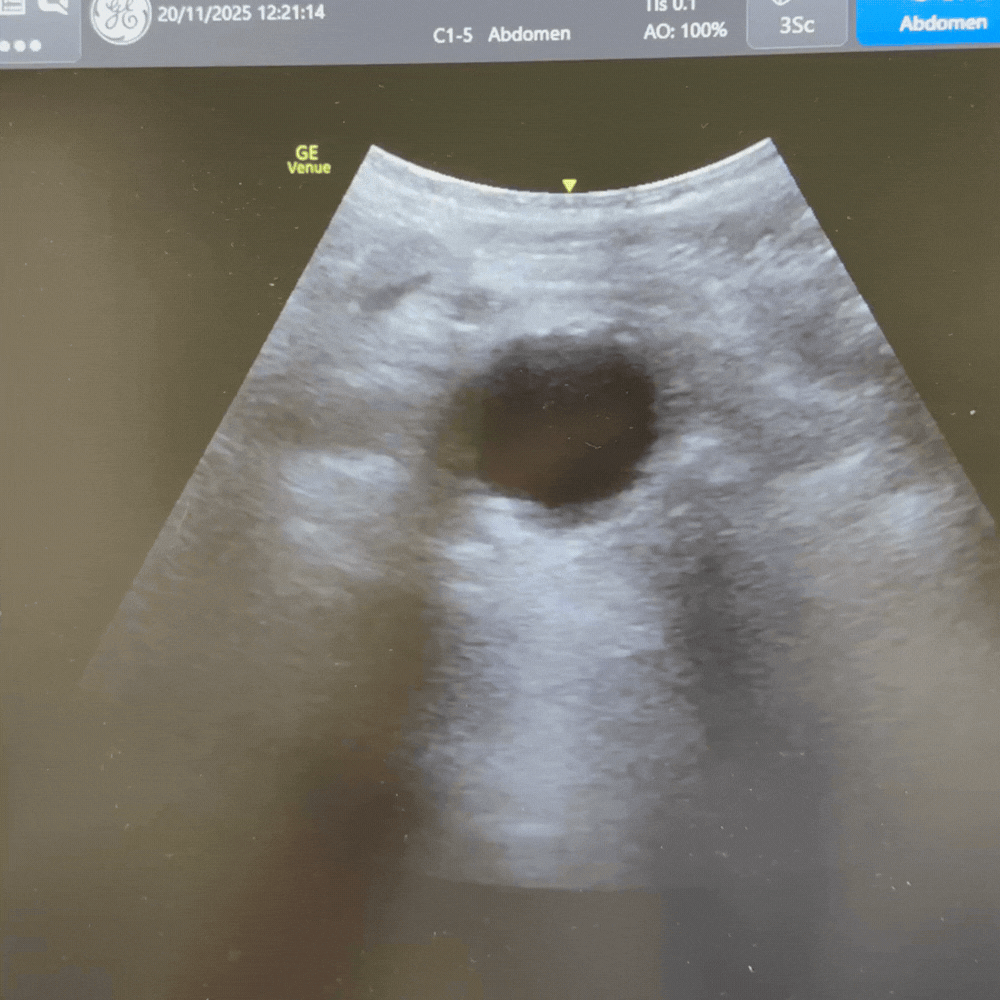

- Lumen anéchogène avec paroi fine et régulière.

- Ramifications visibles : artères rénales, puis bifurcation en artères iliaques.

- Anévrysme fusiforme ou sacculaire : dilatation > 3 cm, souvent avec calcifications pariétales.